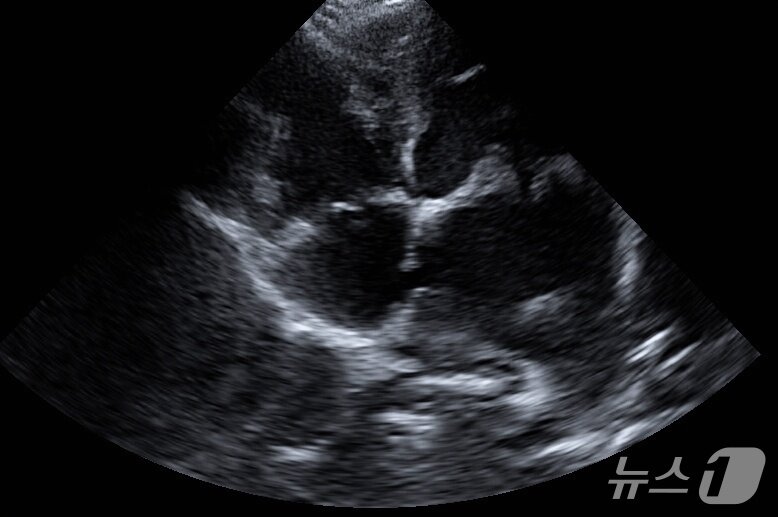

본문 이미지 - 강아지 초음파 검사 결과 심방중격 부위가 터진 모습(더케어동물의료센터 제공) ⓒ 뉴스1

강아지 초음파 검사 결과 심방중격 부위가 터진 모습(더케어동물의료센터 제공) ⓒ 뉴스1